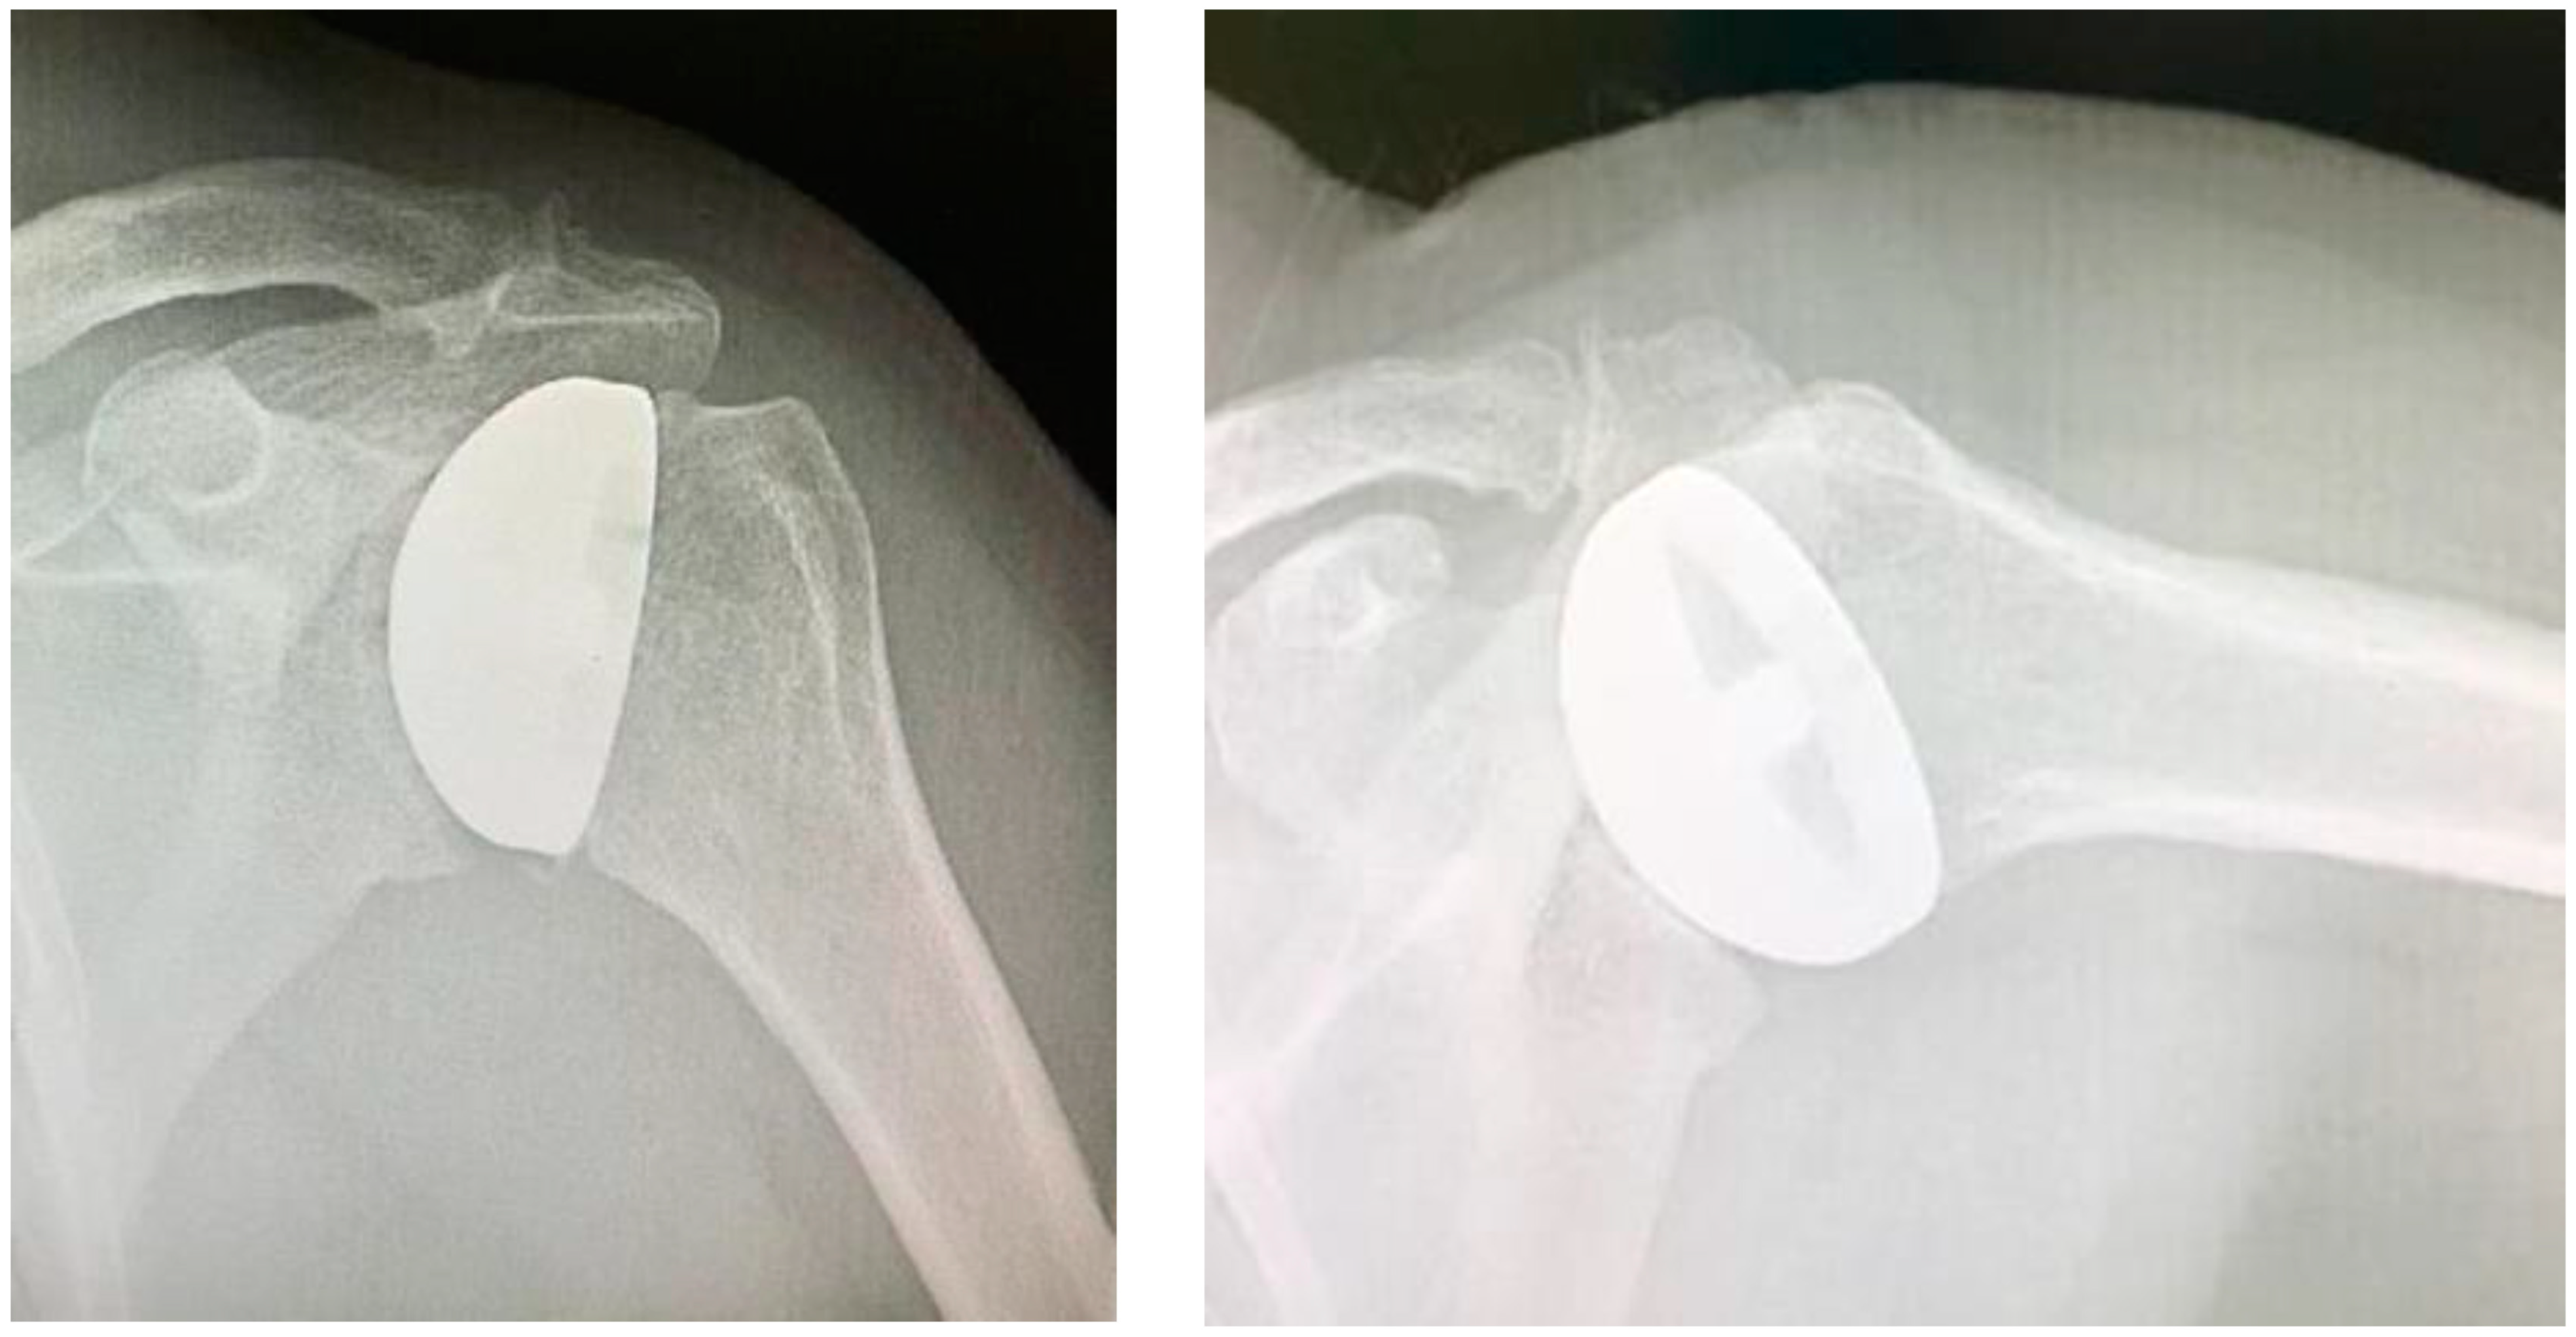

Study design. A retrospective and observational study was performed. The inclusion criteria were as follows: patients with (1) a diagnosis of glenohumeral degeneration with rotator cuff integrity following primary osteoarthritis (Figure 1) or rheumatoid arthritis or avascular necrosis of the humeral head, (2) glenoid articular surface type A1 or A2, according to Walch’s classification [17,18], (3) more than 60% residual humeral head [4,12], (4) who underwent HRA (Figure 2) operated on by a single surgeon and (5) who completed a minimum clinical and radiological follow-up of 2 years.

Figure 2. Avascular necrosis of the humeral head treated with HRA.